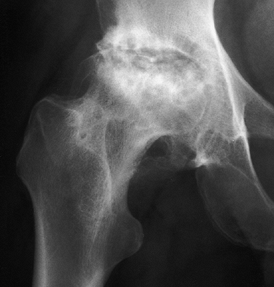

Figure 125.10. Images of a young patient with stage I, steroid-induced osteonecrosis of the right femoral head. A: The plain radiograph is within normal limits. B: The T1-weighted MRI shows a decreased signal intensity in the femoral head, characteristic of osteonecrosis.

|